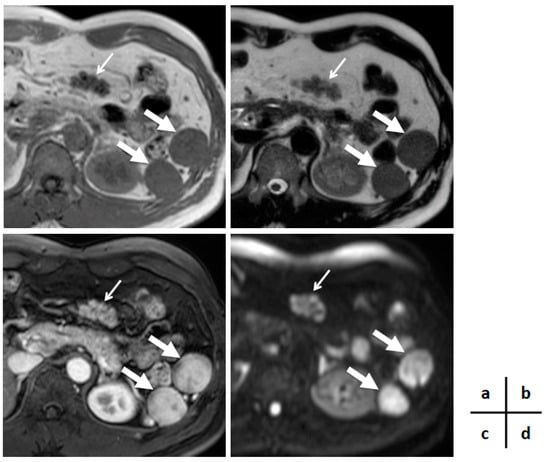

2. Case Presentation